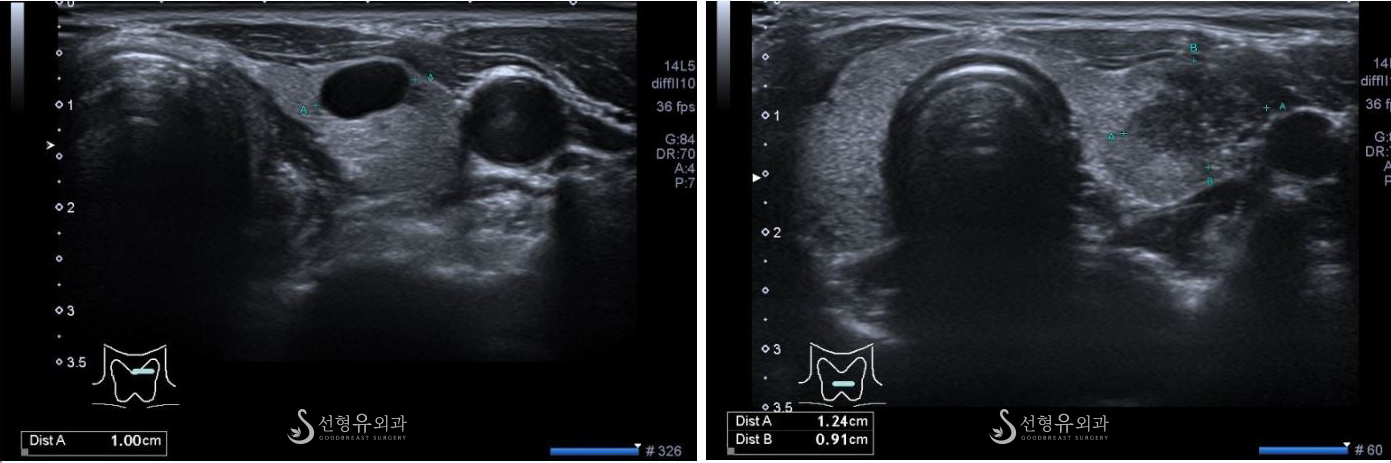

좌측의 혹은 경계가 아주 좋은 타원형으로 양성 소견

우측의 혹은 울퉁불퉁하고 경계가 좋지 않으며 내부도 얼룩덜룩한 모습 (갑상선암 진단)

갑상선 종양 유무를 판단하는 기본 검사는 갑상선 초음파입니다.

초음파 검사를 통해 갑상선 종양이 발견되면 종양의 크기, 모양, 성질을 고려하여 물 혹 같은 양성 종양으로 판단된다면 더 이상의 검사는 필요치 않습니다.

초음파 검사 만으로는 양성 종양인지 악성 종양인지 감별이 안될 시에는 추가적으로 가느다란 주사 바늘을 이용한 세침흡입세포검사를 받게 됩니다.